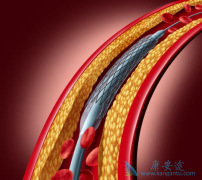

心脏支架手术 ,又被称之为冠状动脉支架植入手术,目前是冠心病的最重要治疗方式之一,手术期间需要在患者的冠状动脉处放置支架以拓宽狭窄的血管壁,使冠状动脉复通并使血液正常的流动,目前在三种情况下建议尽快进行心脏支架手术。情况一:患者的血管 ...

为了改善冠心病介入治疗短期和长期的疗效与安全性,所以研发了支架。第一代支架是金属裸支架,使冠心病介入治疗前进了一大步,使介入治疗变得非常安全,当血管发生严重狭窄时单纯球囊扩张预处理后,再用支架把血管完全撑开,就能解除心肌缺血危险,而且 ...

心脏支架 能管多少年?要回答这个问题,首先要知道心血管中放入支架的目的和作用是什么?所谓心脏支架,就是要在堵塞的血管中搭起一个架子,使原本不能顺畅流动的血液能够更好流通的一种方法,而血管为什么是发生堵塞,是由于发生了动脉粥样硬化或有斑 ...

心血管支架在冠心病患者中应用得最为普遍,当冠状动脉因为粥样硬化狭窄时,心血管支架就可以快速解决血管的梗阻,使血液恢复流畅。但是心血管支架的安装并不是一劳永逸的,一般来说,如果没有禁忌症或副作用, 心血管支架术 后患者需要按医嘱服用以下药 ...